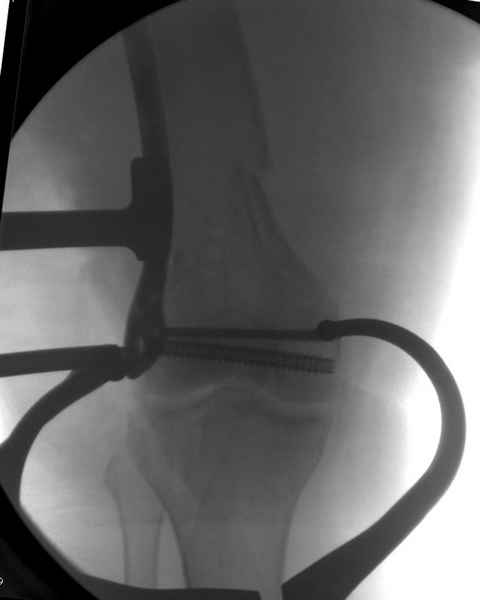

При наличии различных имплантов, любые варианты: слева (полу) открытым - мининвазивным, а справа закрытым интрамедуллярным методом, его считаем более чем приемлемым для фиксации данных переломов.

Проксимальная и дистальная блокировка, независимо от техники введения штифта, ретроградно или антеградно, гарантирует сращение сегментарных переломов бедра без укорочения. Штифты диаметром 12 мм с блокировкой сверху и вниз двумя шурупами выдерживают вес 75 кг больного, что позволяет раннюю профилактику контрактур.

Погоня за "красивой рентгенограммой" не всегда оправдана для фиксации кости, где имеется массивное мягкотканое покрытие. Если так уж хочется исправить положение кости, то при наличии ЭОП, большие костные фрагменты могут быть развернуты или приближены к основному фрагменту методом применения Joystick.

Из-за вариабельности установки дистальных шурупов и возможности перкутанного введения проксимально предпочитаем DePuy Polyax, хотя на сегодняшнем маркете множеств вариантов фиксации дистального бедра перкутанном методом.